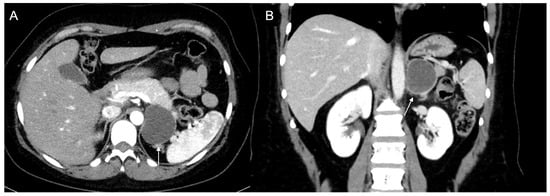

Figure 9.

Voluminous lesion (arrow) of the left adrenal gland measuring 60 × 55 mm with density value > 20 HU on basal CT (A) and inhomogeneous enhancement on venous (B) and late post-contrast phases (C) due to the presence of necrotic and cystic areas. Histological diagnosis of Adrenocortical carcinoma.